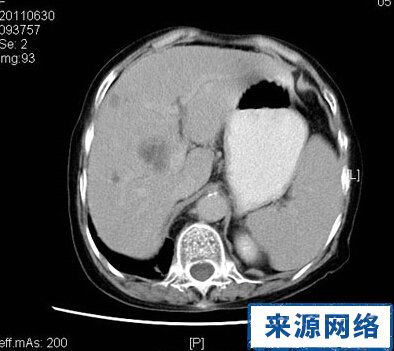

肝囊肿ct图片报告,肝囊肿ct图片

要求给予治疗,从ct检查来看,肝内多发囊肿,最大者左右肝各一12cm直径

(付女士ct检查,左显示乳腺癌术后肝转移瘤,右显示肝囊肿)

肝囊肿ct图(2)(2/5)